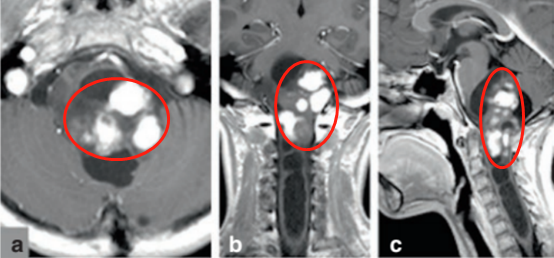

当时看到她拍出来的核磁,我们都吓了一跳,冷汗直接下来了,这个肿瘤已经把脑干吃掉了,还延伸到了颈髓,基本相当于地狱难度。这个手术我们没把握做的,立刻就叫家属带孩子去上级医院...